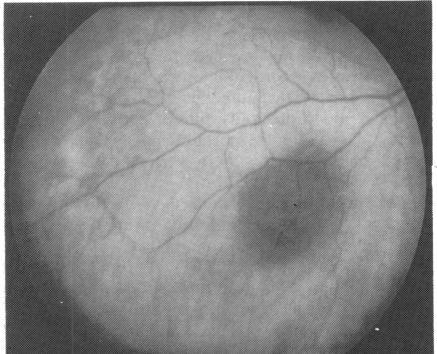

A 52-year-old woman was found to have a small juxtapapillary pigmented lesion in the choroid of the left eye. This lesion remained clinically stationary for one year, but subsequent growth prompted enucleation of the eye. The tumour was diagnosed histologically as a choroidal malignant melanoma of mixed cell type. Approximately 52 months later the patient developed proptosis of the contralateral (right) eye. Orbital ultrasonography showed a large mass in the right orbit, which was confirmed by needle biopsy to be a melanoma. In addition the patient was found to have metastatic melanoma to the choroid, right lower eyelid area, and liver. The development of simultaneous orbital, choroidal, and eyelid metastases from a contralateral choroidal melanoma is of ophthalmic interest and appears to be unique.

摘要